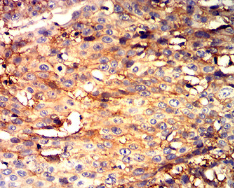

CD298 Mouse Monoclonal antibody[2B3G1]

IHC    1/200 - 1/1000